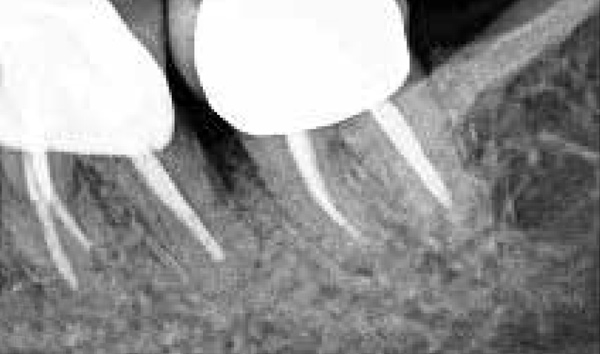

The consensus report from the AAP's work-shop group on intrabony defects presents evidence that periodontal regeneration in intrabony defects is possible on previously diseased root surfaces, demonstrated by gains in clinical attachments, reductions in periodontal pocket depths, gains in radiographic bone heights, and overall improvements in periodontal health.9 These clinical findings are consistent with available histologic evidence, and the clinical improvements can be maintained over long periods of time (ie, > 10 years).9 Although bone replacement grafts have been a commonly investigated modality, guided tissue regeneration, biologics, and combination therapies have also been shown to be effective. Early management offers the greatest potential for successful periodontal regeneration.9 Figure 9 through Figure 11 depict the treatment of a tooth with probing depths of equal to or greater than 15 mm using mineralized FDBA.

(9.) Pretreatment radiograph of tooth with probing depths of equal to or greater than 15 mm.

Figure 9

(10.) Intrasurgical photograph of treatment with mineralized FDBA and EMD.

Figure 10

(11.) Postoperative radiograph taken 4 years after treatment, demonstrating 3- to 4-mm probing depths.

Figure 11